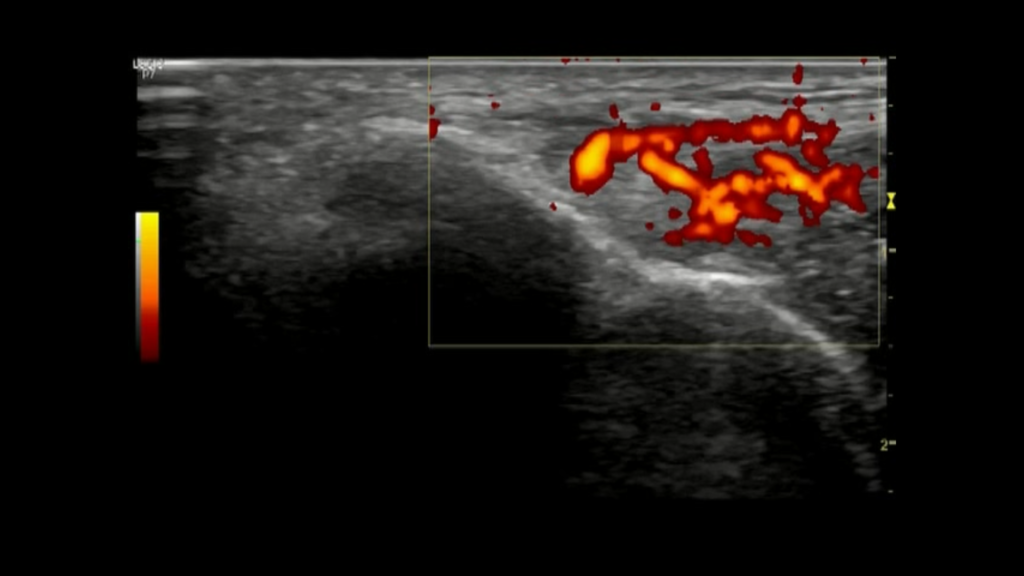

nierówności warstwy korowej kości ramiennej, osteofity, utrata ciągłości i hiperwaskularyzacja ścięgna (zdj. 3) oraz obecność zwapnień.